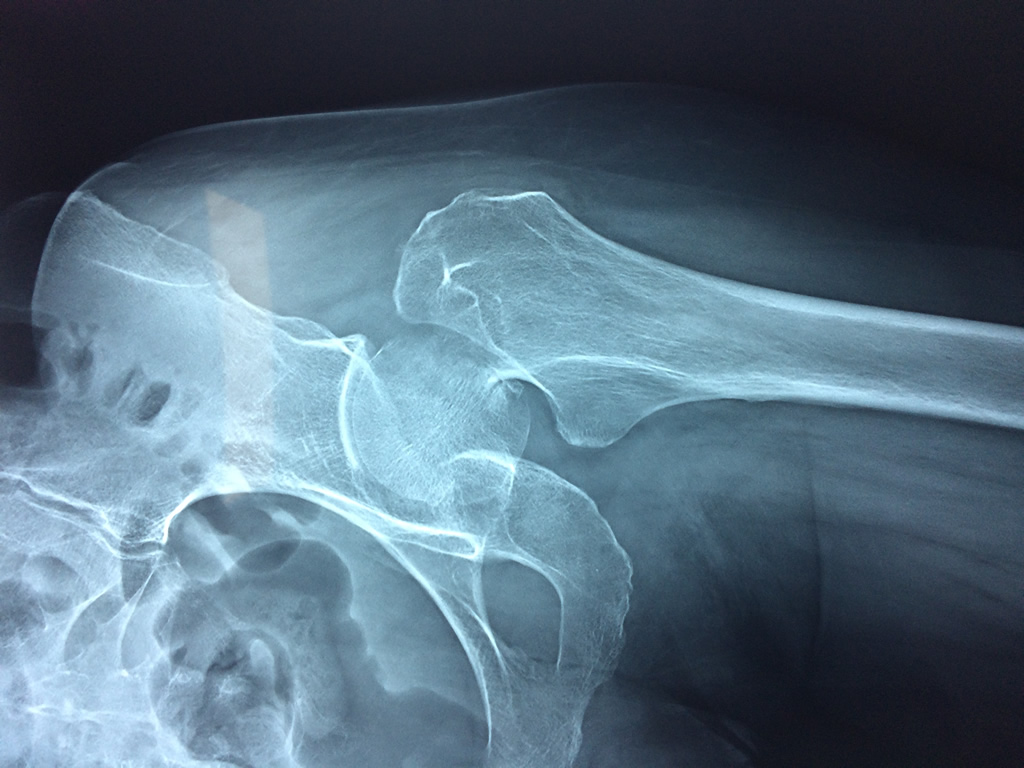

La cirugía de fractura de cadera se realiza para reparar una ruptura en la parte superior del hueso del muslo. Este hueso se denomina fémur.

Es parte de la articulación coxofemoral. Si una fractura de cadera no recibe tratamiento, es posible que deba permanecer en una silla o en la cama.